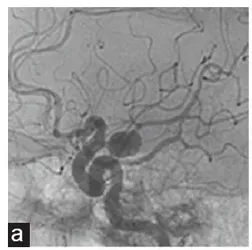

23岁,本该是肆意享受青春的年纪,Emma却活在生命的倒计时中她的颅内埋着一颗被称为脑动静脉畸形(AVM)的大麻烦。 一次突发脑出血后,她因畏惧开颅选择了伽马刀治疗,却没想到4年后,恐...